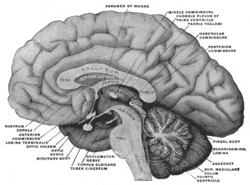

Mesal aspect of a brain sectioned in the median sagittal plane. | |